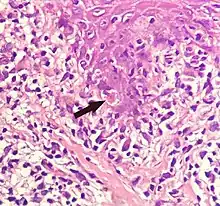

Civatte body

A Civatte body (named after the French dermatologist Achille Civatte, 1877–1956)[35] is a damaged basal keratinocyte that has undergone apoptosis, and consist largely of keratin intermediate filaments, and are almost invariably covered with immunoglobulins, mainly IgM.[36] Civatte bodies are characteristically found in skin lesions of various dermatoses, particularly lichen planus and discoid lupus erythematosus.[36] They may also be found in graft-versus-host disease, adverse drug reactions, inflammatory keratosis (such as lichenoid actinic keratosis and lichen planus-like keratosis), erythema multiforme, bullous pemphigoid, eczema, lichen planopilaris, febrile neutrophilic dermatosis, toxic epidermal necrolysis, herpes simplex and varicella zoster lesions, dermatitis herpetiformis, porphyria cutanea tarda, sarcoidosis, subcorneal pustular dermatosis, transient acantholytic dermatosis and epidermolytic hyperkeratosis.[36]